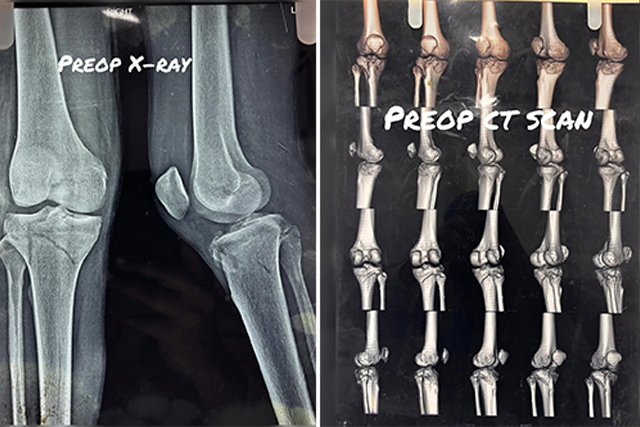

Open reduction and internal fixation (ORIF) for Polytrauma Fixation